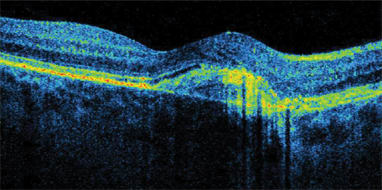

SDOCT does not skip or miss data points, as time domain OCT does because of its speed limitations. Thickness data between time domain scan lines is not actually measured, and values must be interpolated. No interpolation is needed with SDOCT. "We can see pathology that time domain OCT would have missed," Dr. Sharma says. "For example, SDOCT detects drusen or areas of subretinal fluid (Figure 1) that would have fallen between scans on time domain OCT. Also, it is much easier to discriminate pathology with SDOCT technology. For example, it is easier to discern the presence or absence of epiretinal membranes." (Figure 2)

Figure 1. The Copernicus' spectral domain optical coherence tomography maps wet AMD with PED subretinal fluid.